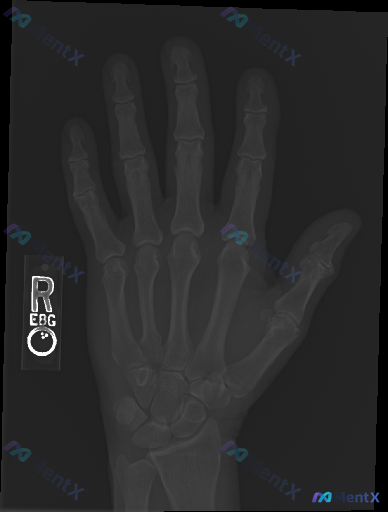

整理到一个值得讨论的影像相关情况: 病例背景 一份右手正位X光片,常规影像学评估结果如下: - 各指骨、掌骨、腕骨骨皮质连续性未见明显中断,无明确骨折线、隐匿性骨折征象或骨膜反应; - 各掌指、指间关节及腕骨间关节间隙基本正常,对位良好,无脱位半脱位; - 骨质密度分布均匀,未见明显骨质疏松、骨质硬...

看到一个挺有迷惑性的病例,整理出来和大家分享一下,整个分析思路也整理好了,很容易踩坑。 病例基本信息 - 基本情况:37岁女性,1型糖尿病,规律胰岛素治疗 - 主诉:右手、右前臂剧烈深沉锐痛1周 - 病史:疼痛出现前1周右前臂摔倒,仅轻微瘀伤,疼痛程度和外伤程度明显不匹配 - 体格检查:右手右前臂较...